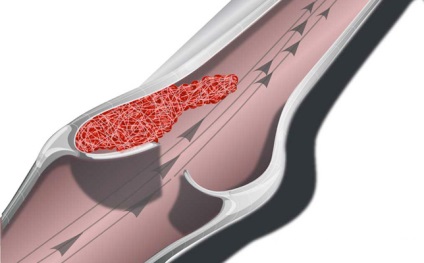

Vénás pangást több neve is van. A gyakorlott szakember használhatja a „öblítés” azt jelenti, hogy a vérellátás, hogy egy adott szerv vagy testrész. A meghatározott „vénás” ez azt jelenti, hogy a beteg vénás torlódás fordul elő. Ő szegény vér áramlását a vénákban, de ugyanakkor véráramlás normális. vér pangás szinte mindig vezet a fejlődés a kóros folyamatokat.

Ahhoz, hogy a vér áramlik át a hajókat, amikor beköltözött a helyes irányba, a szelepek bennük. Ezek szabályozzák a véráramlást, és irányítják őket a szerzés a szívbe. A belégzés stimulálása a vérkeringést, de ez nem elég. A fontos szerepet játszott a szív, de ez még mindig a legfontosabb az, hogy a munka az izmokat. Látnak a funkció a szivattyú és ellenőrzik a préselés vér érintő szelepeket a vénákban. Nem lehet megváltoztatni az irányt a vér áramlását.

Stagnálás vénás vért kezd megjelenni növekvő sűrűsége és romlása véredények rugalmasságát. Így mozog kevesebb, mint a vénákban. Az orvosok minősítette többféle vénás pangás. Ez akkor fordulhat elő, a tüdő, fej, lábak és kismedencei.